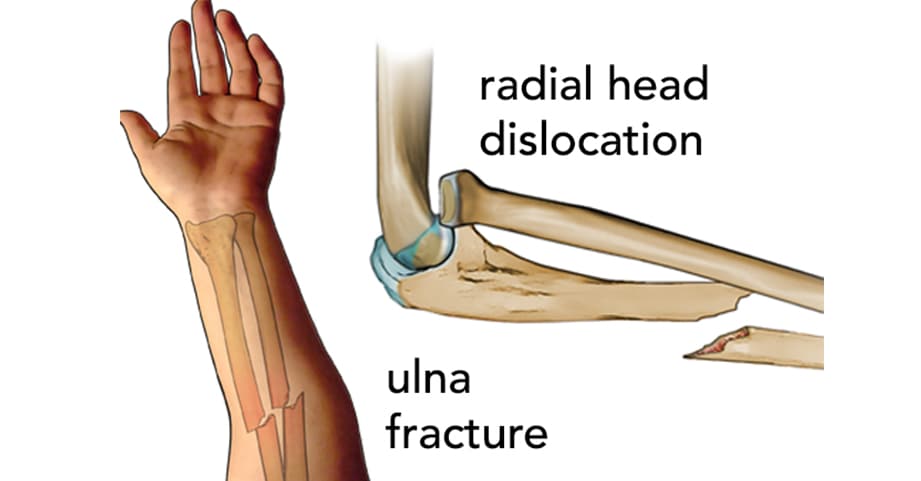

Product Name: Fractured arm saleBroken Arm Fractured Arm Symptoms Treatment Recovery sale, Adult Forearm Fractures OrthoInfo AAOS sale, Hand and Arm Fractures Children s Hospital Colorado sale, Broken arm Altru Health System sale, Forearm Fractures in Children OrthoInfo AAOS sale, Arm Fracture Injury Compensation Claims McCarthy Co sale, Broken Arm Signs Symptoms Treatments Orthopedic Sports Medicine sale, Broken Arm Treatment Austin TX Dr. Gregg Vagner sale, Understanding a Humerus Fracture Saint Luke s Health System sale, Humerus Fracture Upper Arm Fracture Johns Hopkins Medicine sale, Arm Fractures Hairline Fractures More sale, What to Expect During Broken Arm Recovery OC Sports Rehab sale, First Aid Advice For Treating A Broken Arm sale, Adult Forearm Fractures OrthoInfo AAOS sale, Fractured arm and hand bones Stock Image C021 0781 Science Photo Library sale, Research Reveals Issues With Fracture Healing In People With Down Syndrome Texas A M Today sale, Emergency Aid and Treatment for Compound Arm Fractures sale, Broken Arm Symptoms Causes and Treatment Tanya Coats sale, Fractured arm and wrist bones Stock Image C021 0782 Science Photo Library sale, Coping with a Broken Arm Understanding Treatment Recovery Singapore Sports And Orthopaedic Clinic sale, How to Splint a Broken Arm With Cardboard sale, Pediatric Arm and Elbow Injuries Children s Healthcare of Atlanta sale, Broken Arm Orthoanswer sale, Broken Bone and Fracture Causes Symptoms Treatment UPMC sale, 3 780 Broken Arm Xray Royalty Free Images Stock Photos Pictures Shutterstock sale, Broken Arm X ray 1 Poster sale, Is my broken arm supposed to hurt so much r brokenbones sale, Kid s Forearm Fracture Raleigh Hand Surgery Joseph J. Schreiber MD sale, Broken Arm Here s What You Need to Know Louisville Bones sale, Fore Arm Fracture Drsinghphysiocare sale, Orthopaedic Trauma Fracture Specialist in Melbourne br sale, Broken Arm Types Symptoms Causes and Treatment sale, Broken arm X ray Stock Image C010 3591 Science Photo Library sale, Broken Arm Signs Symptoms Treatments Orthopedic Sports Medicine sale, Emergency First Aid for a Broken Arm sale.